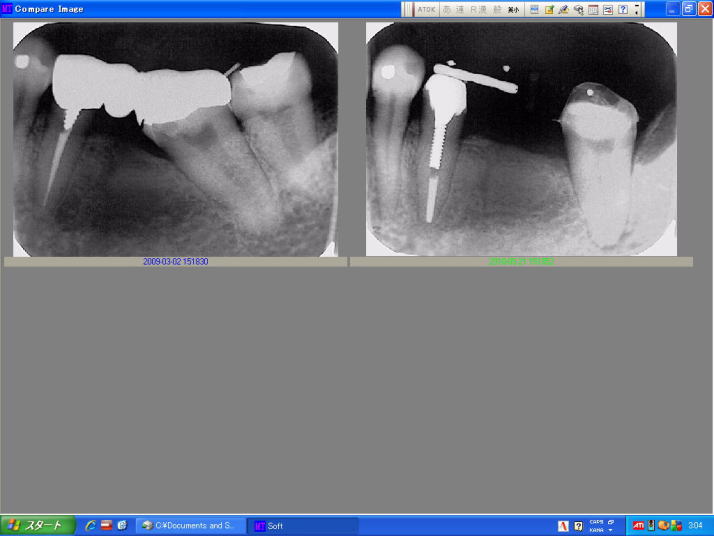

Client(Wireless LAN)         Serverでの画像診断は、Dual Monitorで効率よくできる          経時的比較が容易

(800×600Pixels.48.0KB)